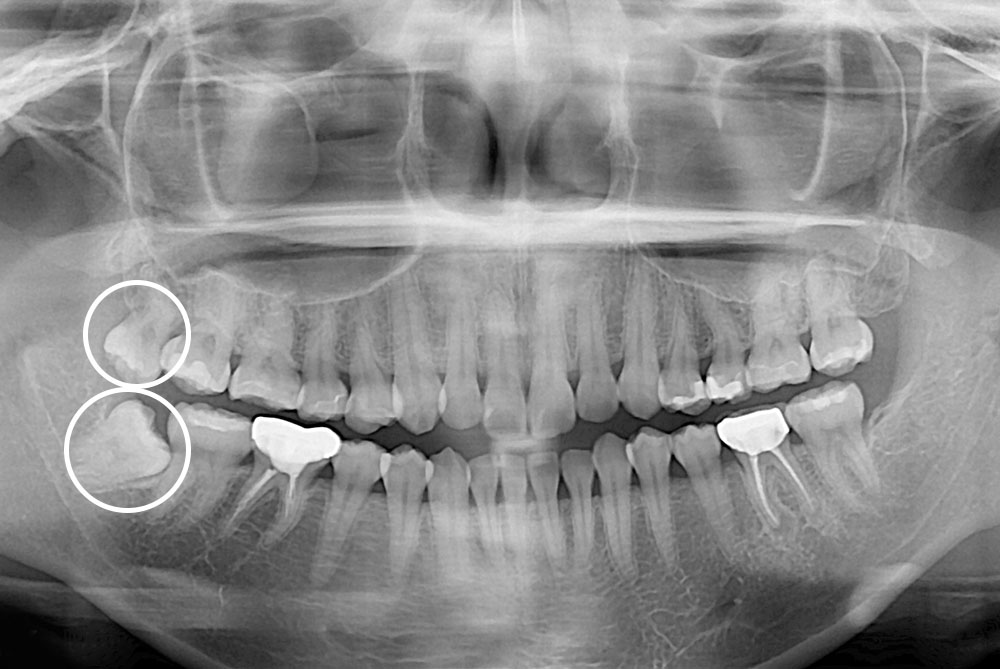

[사랑니] 매복 사랑니 발치

치료전 : 2019-07-08